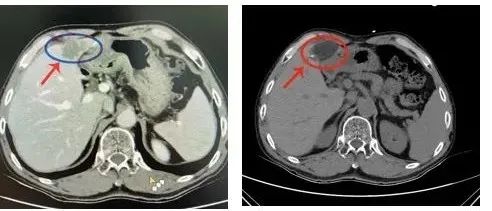

近年来肿瘤的发病年龄越来越年轻化,大家已经开始逐渐重视它。穿刺活检是肿瘤治疗过程中非常重要的一步,肿瘤患者需要选择那些手段治疗,往往有赖于穿刺活检得到的病理结果。首先:看片子做出的诊断叫做“影像学诊断”,只能凭经验初步判断是不是肿瘤,但是具体是哪一种类型的肿瘤,有没有基因突变都不得而知,后面的治疗用药也会盲目。所以,穿刺以后得到的病理结果是医生确诊的金标准,比如下面肿瘤科的这个患者:

这个年轻的患者如果当时不去做穿刺活检,就会被当成一个肝转移骨转移的晚期肿瘤患者对待,经过穿刺活检,提示他只是一个肝脏结核造成的骨破坏,所以说病理活检是多么必要!

国内外大量的研究证明,在操作中恰当的保护措施,种植转移的概率完全可以忽略不计,尤其我们肿瘤科开展的同轴活检技术,更是大大避免您的忧虑。以前的活检技术直接穿刺扎到肿瘤,容易造成“拔起萝卜带泥”,现在的我院开展的同轴活检技术,只需要进针一次,多次多角度取材,同时进行针道封堵,取材量比以前要大,避免了针道转移,减少患者痛苦!